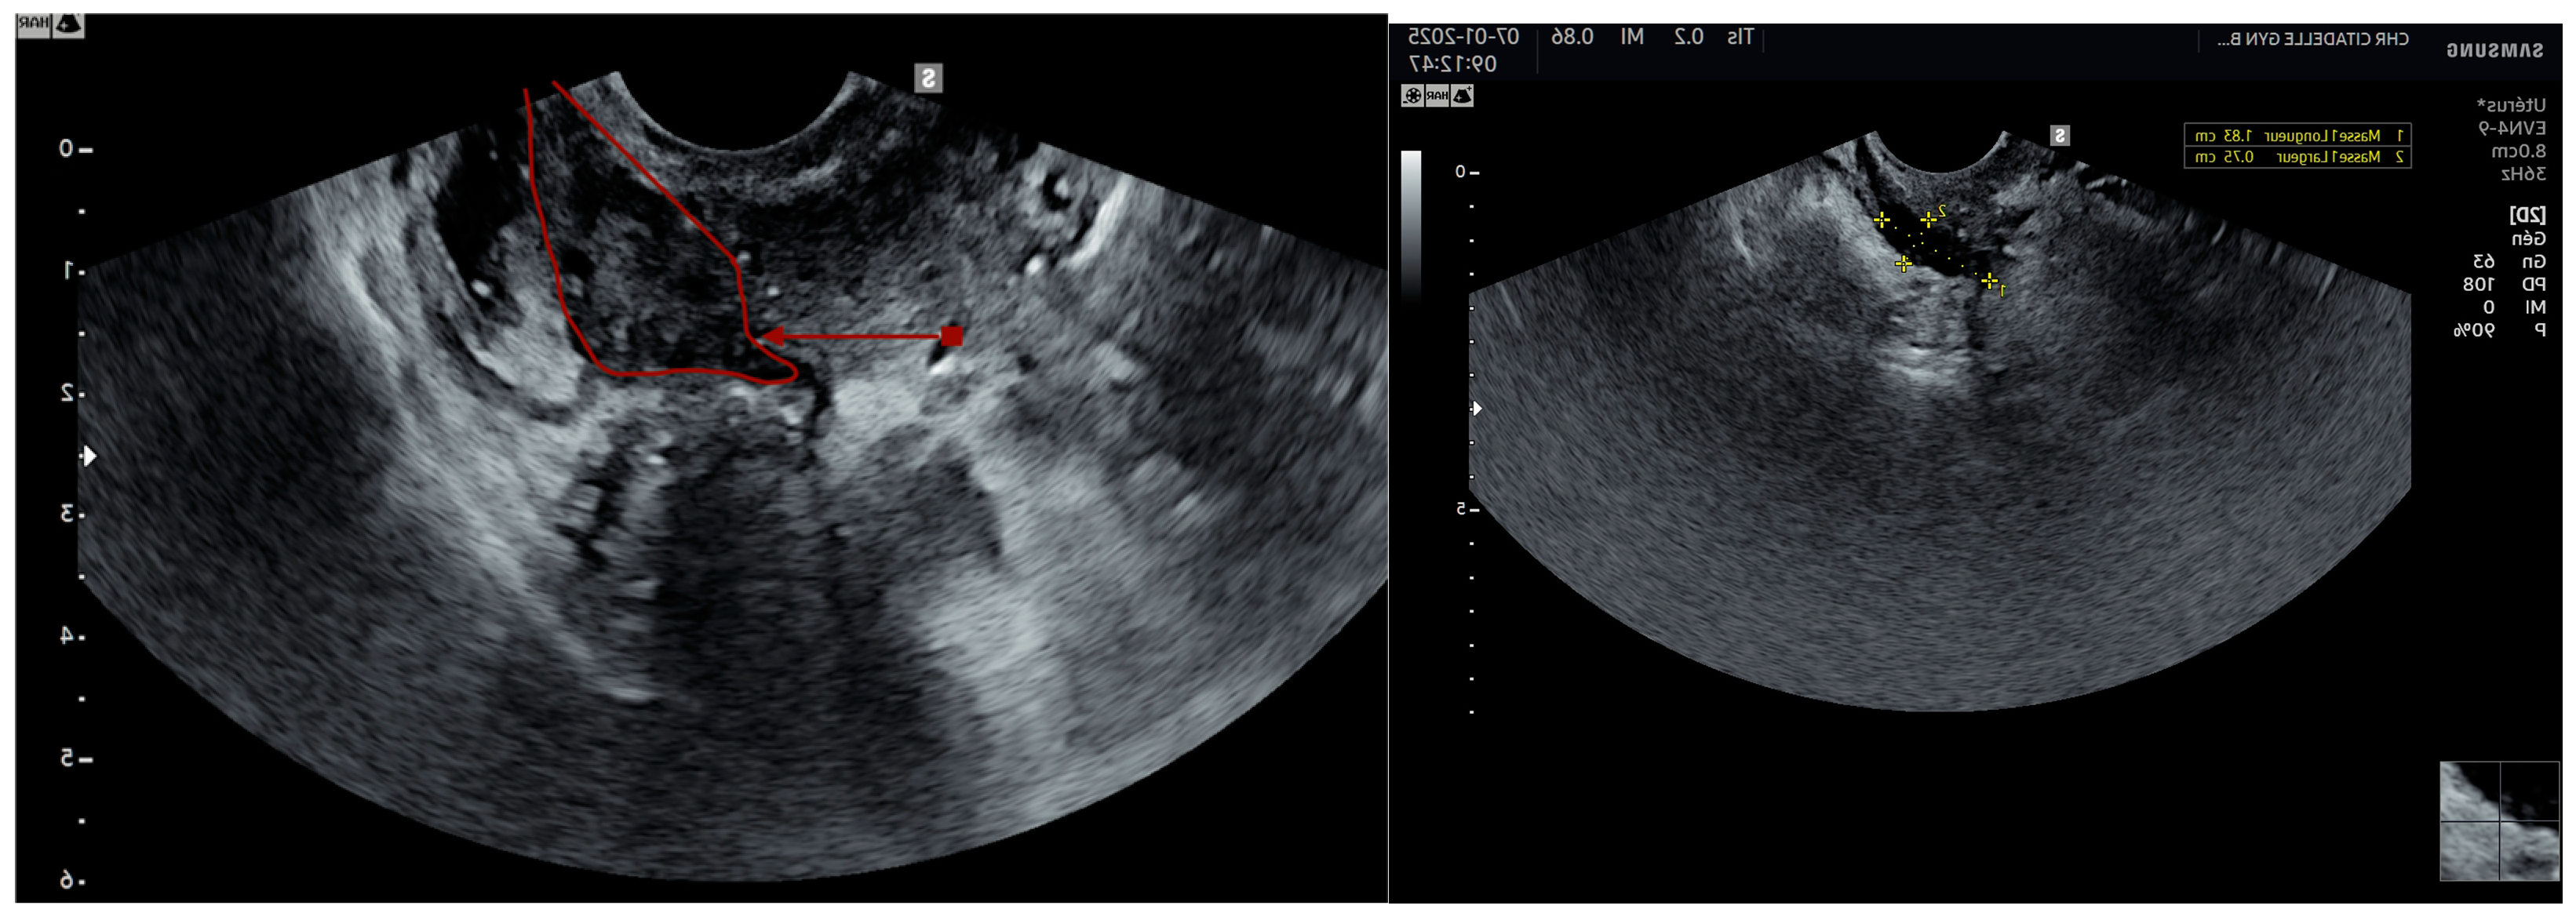

4. Ultrasound

- Endometriomas (number, size, kissing ovaries)